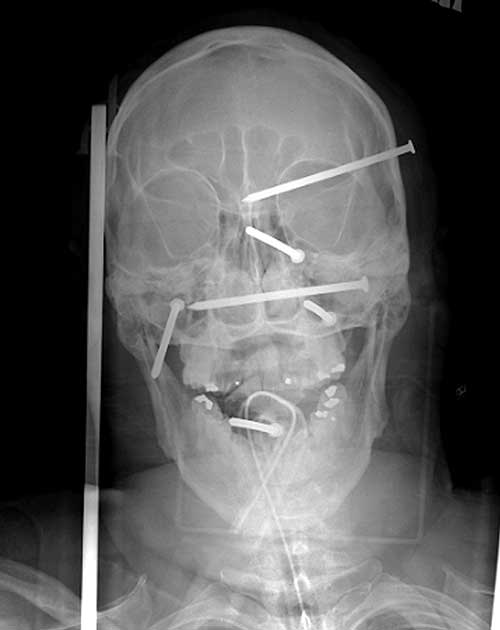

And here are the amazing photos — actual x-rays of Isidro Mejia’s injuries. He is expected to make a complete recovery. It took four days to remove all the nails in delicate surgeries, taking care not to create additional damage.

Wow, that’s incredible that he survived and was expected to make a full recovery, seeing those x-rays!

Indeed! Those aren’t little finishing nails. -rc